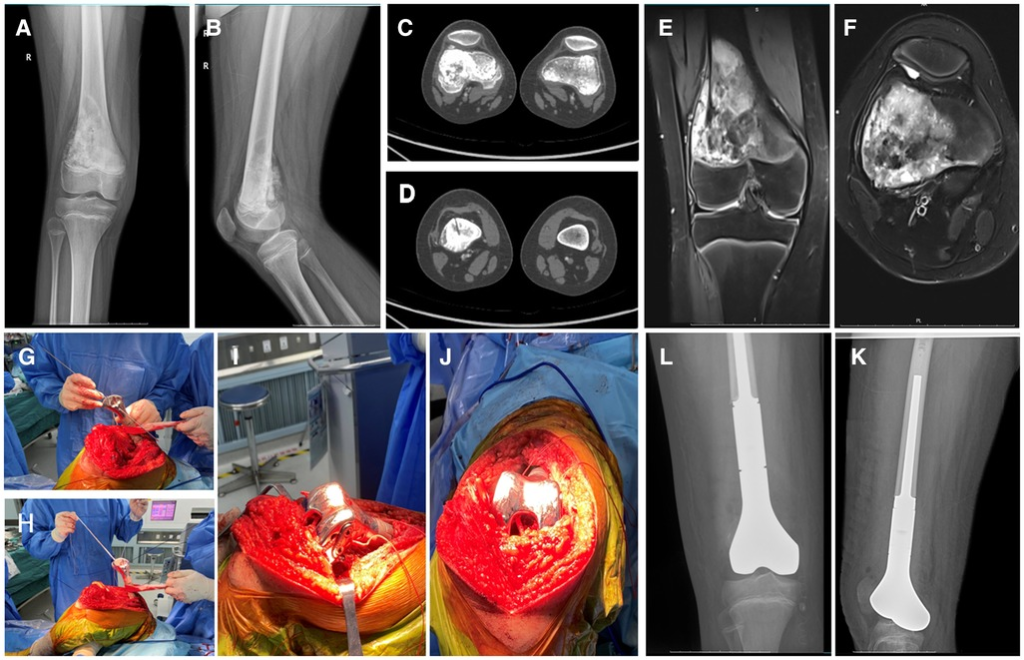

Limb preservation (salvage) surgery aims to remove malignant bone or soft tissue tumors while preserving the limb’s function and appearance, avoiding amputation in over 90% of cases today. Performed after neoadjuvant chemotherapy, it involves wide tumor resection with clear margins, followed by reconstruction.

Endoprosthesis (Megaprosthesis): Custom or modular metal implants replace resected bone/joint, ideal for peri-articular tumors.